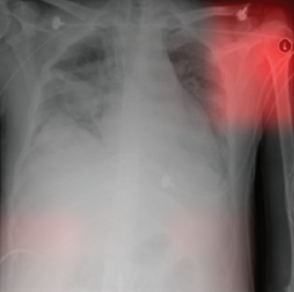

Geirhos et al. showed that a deep learning model failed to recognize pneumonia from X-ray scans of a new hospital because the model learned to predict pneumonia based on hospital-specific attributes[Geirhos2020]. Using state-of-the-art techniques in explainable AI, DeGrave et al. demonstrate that recent deep learning systems to detect COVID-19 from chest radiographs rely on confounding factors rather than medical pathology, creating an alarming situation in which the systems appear accurate, but fail when tested in a new hospital[DeGrave2021]. Luo et al. illustrate that a DL model trained with radiograph-level annotations is prone to shortcut learning (ie, using unintended patterns for decision-making[Luo2022]. It can be observed that CheXNet’s Grad-CAM might not precisely cover the intended lesions and sometimes even attend to false-positive regions (Fig 1). Studying networks trained with pneumonia datasets, Catalá et al. observed heatmaps often highlighted areas of the image which did not contain lung tissue, rather model learn from simple features like white rectangular box at the top corner [Catala2021]. Jabbour et al. reveal that deep learning models trained on chest X-rays can exploit spurious correlations such as patient demographics, treatments, or preprocessing artifacts, leading to shortcut learning and poor generalization across hospitals[Jabbour2020] (Fig 2).